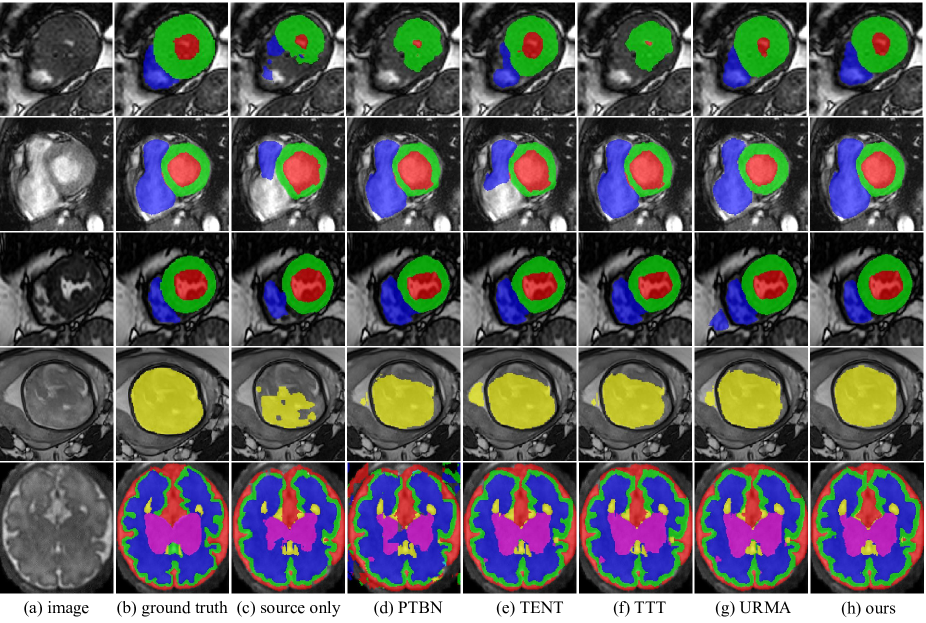

In terms of average Dice values, our method outperformed “Fine-tune valid”, and was close to “Target only” (-value 0.05) in target domain B, and better than “Fine-tune train”, “Fine-tune valid” and “Target only” in target domain C. In target domain D, our method also outperformed “Target only”. Note that “Target only”, and “Fine-tune train” require annotations in the training set of the target domain, while our adaptation method could achieve a similar performance without the annotations. We also analyzed the effectiveness of ensemble of multiple prediction heads with spatial transformations. Taking M&MS B as an example, “Source only-Esb” performed better than “Source only”, indicating the positive effect of additional data augmentations for inference. In addition, “Ours w/o Esb” exhibited a decreased performance compared with our complete method. This suggests that ensembling during inference plays a beneficial role in our approach. A visual comparison between different SFDA methods is shown in Fig. 3. Note that “Source only” achieved a poor performance, and the results of our method were closer to the ground truth than those of the other methods.

We further investigated the performance of the compared methods on FB dataset, with HASTE and TrueFISP as the source and target domains, respectively. The quantitative evaluation results are shown in Table 4. It can be observed that “Source only” and “Target only” achieved an average Dice of 84.09% and 88.85%, respectively, showing the large gap between the two domains. “Fine-tune train” outperformed “Target only”, achieving an average Dice of 89.71%. The existing methods only achieved a slight improvement compared with “Source only”, with the Dice values ranging from 84.12% to 85.84%. In contrast, our method largely improved it to 89.10%, which outperformed “Target only” and was close to “Fine-tune train” (p-value 0.05). Our method achieved an average ASSD of 1.08 pixels, which was lower than those of the other SFDA methods. The qualitative comparison in the penultimate row of Fig. 3 shows that the existing methods tend to achieve under-segmentation of the fetal brain, while our method can successfully segment the entire fetal brain region with high accuracy.

Quantitative evaluation results on the FeTA dataset in terms of Dice are shown in Table 5. It shows that “Source only” and “Target only” achieved an average Dice of 68.30% and 81.27%, respectively, indicating the large gap between the two domains. Our method increased the average Dice by 6.89 percentage points compared with “Source only”, reaching 75.19%. In contrast, the existing methods had a lower performance than ours. The average Dice obtained by PTBN [32], TENT [12], TTT [9] and URMA [21] was 69.53%, 72.64%, 70.90% and 73.79%, respectively. The qualitative comparison in the last row of Fig. 3 demonstrates that our method outperformed the other methods in terms of segmentation performance.